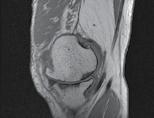

CT-ul cu reconstrucție tridimensională sau RMN genunchi relevă mult mai

bine complexitatea fracturii și dau posibilitatea unui planning preoperator superior estimării radiologice clasice(7). CT-ul este mai rapid și mai ușor de făcut, dar RMN decelează mai bine leziunile de menisc sau ligamentare.

Schatzker III, Osteosinteză cu șuruburi percutană

Schatzker VI, Reducere sângerândă și osteosinteză cu 2 plăci

fracturilor cu separare sau înfundare a platourilor tibiale, precum și a leziunilor de părți moi asociate ligamentare sau de menisc.

Se practică radiografii standard, examinare CT sau RMN.

Radiografiile se fac în cel puțin 3 incidențe: antero-posterioară, laterală și notch intercondilar.

Incidența antero-posterioară poate decela: o bandă osteoscerotică intensificată, specifică fracturii cu înfundare, separarea unui fragment osos, incongruență articulară femuro-tibială. O înfundare mai mare de 6 mm sau/și o incongruență articulară cu lărgirea acesteia mai mult de 5 mm sunt sugestive pentru leziuni de menisc lateral, ligament colateral lateral sau ligament încrucișat posterior(5). O înfundare sau lărgire articulară mai mare de 8 mm este deseori asociată cu o leziune de menisc medial(6).

Incidența laterală decelează traiecte de fractură postero-mediale.

În baza examenului radiologic au fost propuse mai multe clasificări, dar cea mai folosită este cea a lui Schatzker:

În fracturile Schatzker I, fără leziuni de menisc extern asociate este indicată reducerea și osteosinteza percutană cu șuruburi. Dacă leziunea de menisc este evidențiată pe RMN, se poate opta pentru reducere și osteosinteză percutană cu șuruburi asociată cu artroscopie(12), având rol de control al reducerii și curativ pentru leziunea de menisc, sau reducere deschisă și fixare internă cu placă și șuruburi.

La pacienții tineri cu fracturi Schatzker tip II și III se poate opta pentru reducere și osteosinteză percutană cu șuruburi asociată cu artroscopie. O altă variantă este cu grefă osoasă și reducere deschisă cu fixare internă cu placă și șuruburi. Controlul reducerii intraoperator se realizează artroscopic sau cu C arm.